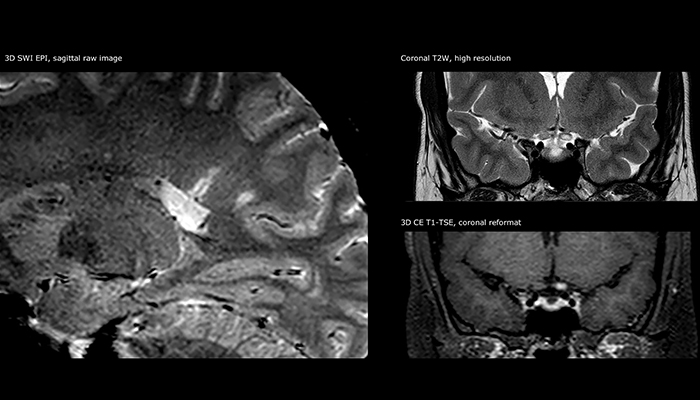

“Ingenia 3.0T provides us very good image quality with high SNR, even if we push the resolution. For example, in FLAIR images we may have an isotropic resolution of 0.9 mm. Ingenia allows us to use 3D T1 TSE with BrainView, which has a better sensitivity than 2D spin echo imaging[2] and 3D gradient echo imaging. Ingenia also provides highly reproducible exams, which is important in MS imaging so that follow-up exams at different time points are done the same way.”

For MS imaging in the brain, Dr. Savatovsky uses 3D FLAIR as the basic sequence to visualize the lesions and assess the situation and lesion load. “We count the lesions in each location to determine if the criteria of the disease are fulfilled. We use a T2-weighted sequence because our neurologists are used to it. We compare the lesion load on FLAIR with a 3D T1 post-contrast sequence to help us determine whether lesions are old or new. We typically administer the contrast before the patient enters the machine because it shortens the examination time and allows to visualize active lesions that tend to be more visible after several minutes. When a differential diagnosis is difficult, we add sequences such as susceptibility imaging, because some focal MS lesions have a small vein in the center[3].”